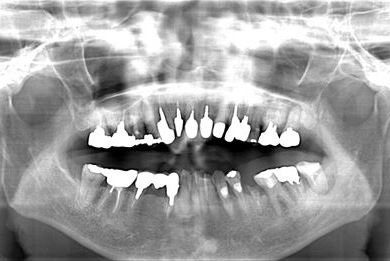

インプラントの症例写真 IMPLANT

抜歯即日スピードインプラント

| 性別/年齢 | 女性 / 61歳 | ||||||||||||||||||||||||||||||||

| 主訴 | 差し歯が取れてしまったところをインプラントにしたい。 | ||||||||||||||||||||||||||||||||

| 治療内容 | インプラント1本(抜歯即日スピードインプラント)、メタルボンドセラミック1本 | ||||||||||||||||||||||||||||||||

| 総治療費 | 437,955円 | ||||||||||||||||||||||||||||||||

| 治療期間 | 5ヶ月 |